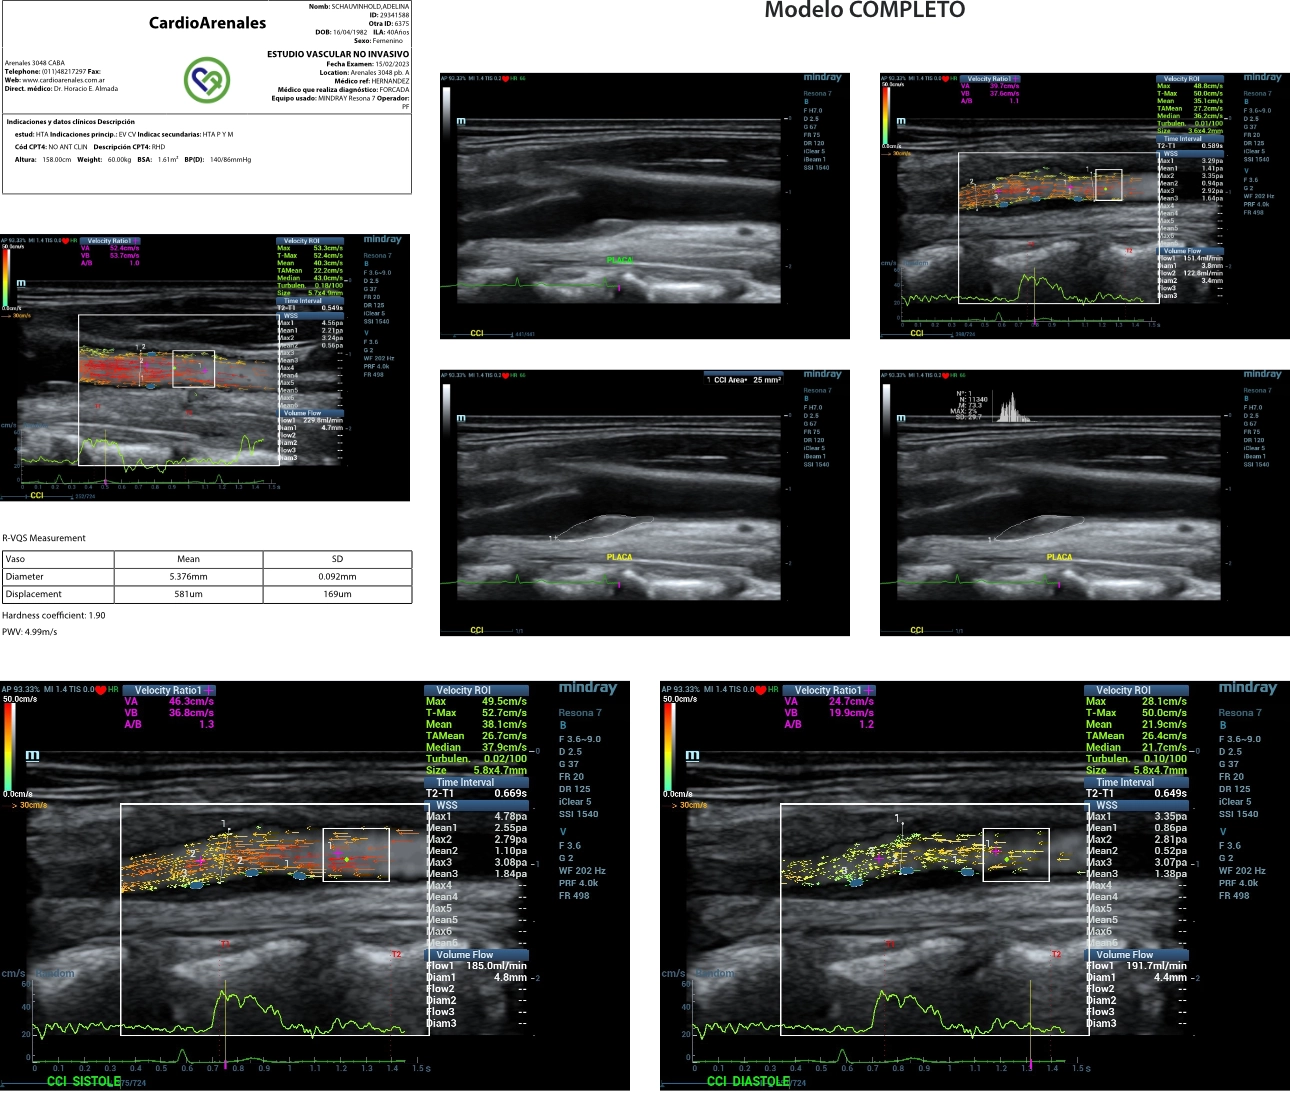

2. US findings: Carotid atherosclerotic plaques in left carotid artery bulb. Evaluations: Complete US investigation of carotid and femoral arteries. Evaluation of Pulse Wave Velocity and endothelial function test using forearm ischemia hyperhemia were performed. Analysis of plaques in left common carotid artery included, plaque area, B Hist plaque composition analysis (Grey Scale Mean GSM), V FLOW parameters speed gradient, flow, WSS and turbulence) and also LCCA were evaluated using V FLOW and RVQS stiffness evaluation (Pulse Wave Velocity (PWV) and Hardness coefficient). (Table 1)

LCCA speed and flow were comparable, but the stiffness was higher in the LCCA of the Stiff plaque (PWV 9,6 vs. 5 m/s and Hardness coefficient 7,6 vs 1,9) compared to soft plaque LCCA. The Stiff plaque showed a smaller area (14 vs 25 mm2), higher GSM (111 vs 73 GS) and lower values of WSS in the proximal shoulder (0,68 vs 1,41 Pa), the tip (0,66 vs 0,94 Pa) and distal shoulder (1,3 vs. 1,64 Pa) than the soft plaque. The pattern of the WSS shows a “depression” in the proximal shoulder of the stiff plaque and in the top center of the soft plaque, probably linked to the expansion of the last one (almost 10% compared with 0% of the stiff plaque, see bulb diameter syst/diast). (Table 1)

The neighboring artery of the hard plaque was stiffer compared with the soft plaque and the expansion of the first plaque lower. At comparable levels of speed and flow and negligible levels of gradient, the WSS behavior was different in the stiff plaque than in the soft plaque, showing different vulnerable regions in each one. These findings could lead to a better comprehension of the development and evolution of atherosclerotic plaques and eventually follow up the response to treatment (statins or specific CV treatments). (Graphics 1 Stiff Plaque Graphics 2 Soft Plaque)

Graph 2 : Different images corresponding to a soft plaque.